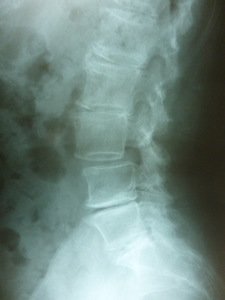

円背と腰痛症

円背が見受けられます 胸椎の代償作用として腰仙角が増大する人と少なくなる人と2通りあります。

胸腰部の圧迫骨折又は遺伝的要素もあり手技療法一番苦労します。

腰痛症で膝の痛み・肩こりも伴います。

いずれにしても少しでも胸椎と腰椎の柔軟性の回復が重要だと思われます。